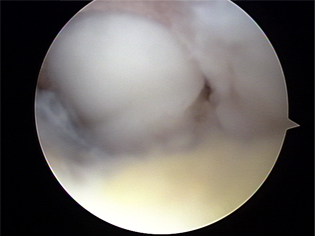

자가연골이식술 1

자가연골이식술 2

자가연골이식술 3